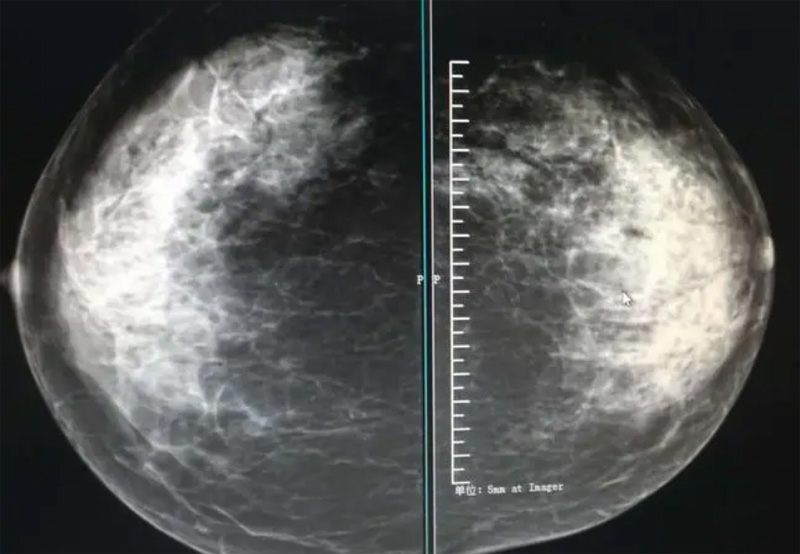

乳腺DR的檢查中為了讓乳腺相關(guān)疾病的篩查需要更高質(zhì)量的檢查圖像。檢查前期的準備工作非常重要。醫(yī)生跟病患的有效溝通。要跟檢查者說明檢查過程,特別是體位跟擠壓乳房帶來的不適應(yīng)。放松心情,檢查過程中得到充分的合作。正確的擺正位置乳腺DR可以拍攝到更優(yōu)質(zhì)清洗高質(zhì)量的X線圖像。乳腺DR檢查需要再月經(jīng)后檢查,但是對病癥明顯的就不受這個限制。

乳腺DR攝影體位有頭尾位及內(nèi)外側(cè)斜位,

乳房在片子的中央,乳頭切線位,可見小部分胸大肌,內(nèi)側(cè)乳腺組織應(yīng)全部包括在片中,外側(cè)乳腺組織盡可能包括在片中。一張好的MLO位圖像顯示如下:乳房被推向前上,乳腺實質(zhì)充分展開,胸大肌可見,較松弛,下緣達到乳頭水平,乳頭在切線位,部分腹壁包括在片中,但與下部乳腺分開,絕大部分乳腺實質(zhì)顯示在片中。乳腺組織外緣可見乳頭的輪廓;乳腺后方的脂肪組織被很好地顯示出來,乳房無皺褶。對于CC位及MLO位顯示不良或未包全的乳腺實質(zhì),可以根據(jù)病灶位置的不同選擇以下體位:外內(nèi)側(cè)位(LM)、內(nèi)外側(cè)位(ML)、內(nèi)側(cè)頭尾軸位(MCC)、外側(cè)頭尾軸位(LCC),尾葉位(CLEO)及乳溝位。在臨床實踐中,對于常規(guī)體位上發(fā)現(xiàn)的異常改變,可以進一步采取一些特殊的攝影技術(shù),包括局部加壓攝影、放大攝影或局部加壓放大攝影技術(shù)。